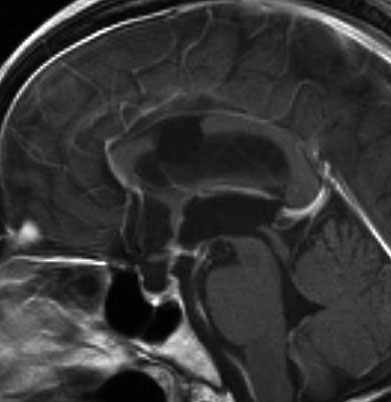

7歳の子が視力障害で発症しました。両耳側半盲という症状です。典型的な鞍隔膜下頭蓋咽頭腫です。ガドリニウム造影剤を入れないMRIでみえる,黄色い矢印の先の白い高信号は抗利尿ホルモンです。ですから下垂体機能もまだ残っていて,尿崩症はありません。視力障害が戻らないことがあるのでなるべく早く,経鼻的な手術で摘出した方がいいものです,簡単 o(^-^)o

9歳児の頭蓋咽頭腫です。視力障害が高度なので鼻の孔(経蝶形骨洞手術)から急いで全摘出しました。腫瘍の塊がトルコ鞍の底にありますが,この部分は開頭手術では多少見づらいです。術後に視力は少し良くなりました。1年後のMRI(右側)では下垂体組織は残っていて,前葉ホルモンは正常ですが軽い尿崩症があります。

矢印の先に見えるように下垂体は正常の形態です。この画像から灰白隆起の左後方,乳頭体の前方が腫瘍発生母地ということがわかります。尿崩症もなく下垂体機能は正常です。経鼻的な内視鏡手術で腫瘍の大部分を摘出すれば下垂体機能は廃絶します。

とにかく失明を避けるために急いで経蝶形骨洞手術(transsphenoidal-transtuberculum sellae approach)で腫瘍のう胞の減圧をしました(緑の矢印の経路 by 函館中央病院加藤功先生)。その後に前頭開頭で腫瘍を全摘出しました(右側の画像)。尿崩症はでましたが下垂体前葉機能は正常です。

成人の第3脳室内部に局在する頭蓋咽頭腫です。経脳梁法で両側のモンロー孔から全摘出しました。下垂体組織は残っています。これは乳頭状頭蓋咽頭腫と呼ばれるもので,成人にしか発生しません,のう胞がなく石灰化もないのが大きな特徴です。境界が明瞭で柔らかく摘出が簡単なタイプとして知られています。この患者さんも術後に下垂体機能不全も視床下部障害も生じませんでした。